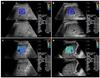

O melhor método de avaliação é a __ (TC/RM).

RM.

Perda do sinal do fígado em paciente com hemocromatose primária acentuada.

Na TC o achado de aumento da atenuação é inespecífico, encontrado também em diversas outras doenças (uso de amiodarona, sais de ouro, doença Wilson)

Vantagens da RM?

• Confirmação diagnóstica;

• Quantificação da sobrecarga férrica;

• Determinar severidade;

• Monitorar terapia;

• Diferenciar hemocromatose primária e secundária.

Graduação da sobrecarga férrica na RM.